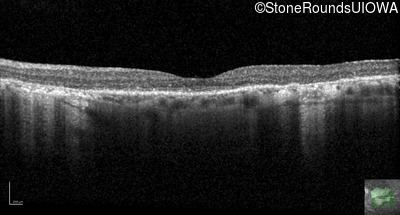

AR Stargardt Disease (IIA)

Age at visit: 69 years

This 69 year old man had excellent vision until 7 years ago when he first noticed some difficulty in dim light especially while driving.

AR Stargardt Disease ABCA4 Trp1101Stop TGG>TAG IVS30+1321 A>G AR